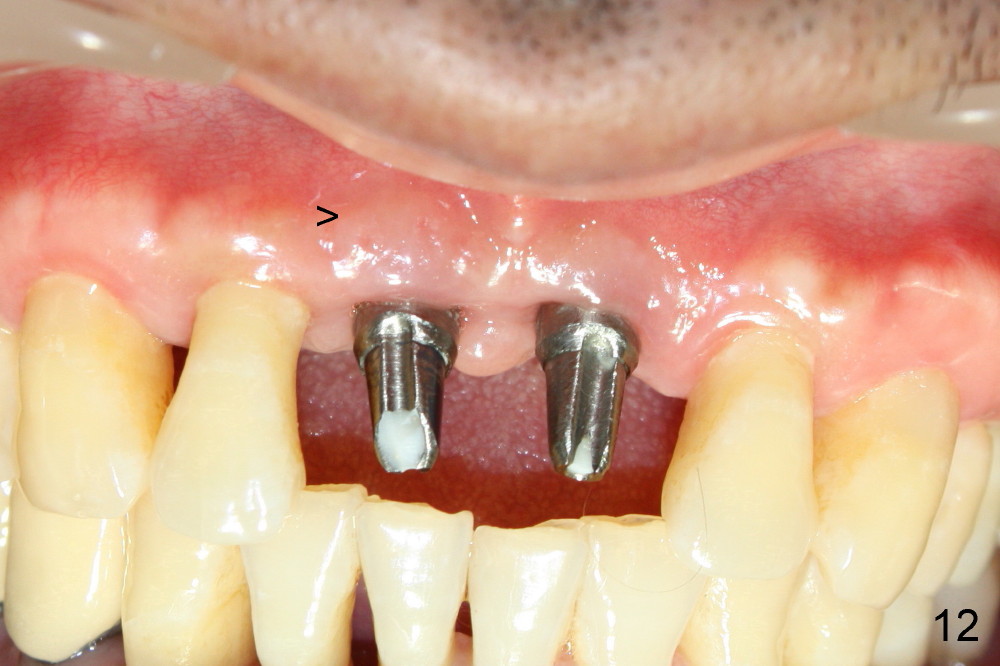

The patient returns for follow up one month and a half after implant surgery. The gingiva around the implants looks healthy. No infection relapses (Fig.12,13: <).